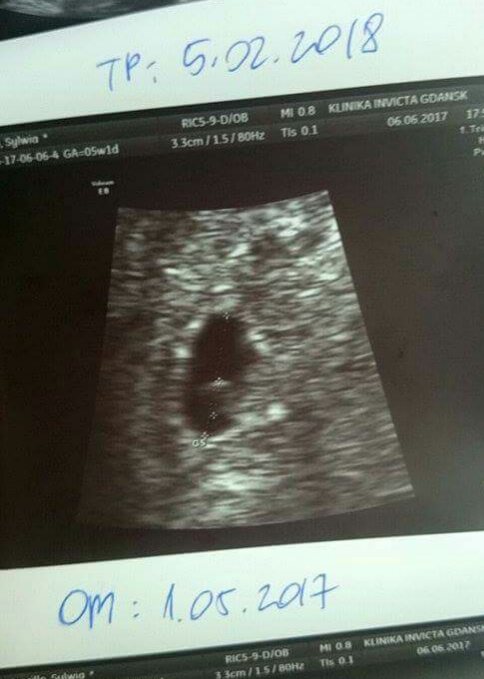

Sylviia i Twoja fasolinka jest śliczna :)